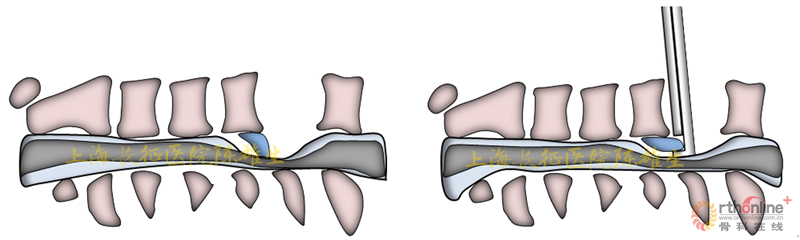

3.2.2骨化物漂浮,初步缓解脊髓压迫

磨钻磨透骨化物周围骨结构;剥离子游离骨化物边界,使之漂浮,初步缓解脊髓压迫(图13)。

图13

3.2.3椎体后壁-骨化物整块切除,彻底减压:

把持骨椎体后壁,远离脊髓逐步抬起;直视下观察骨化物与硬膜囊关系;神经剥离子分离粘连结构(图14)。

图14